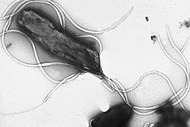

H. pylori is a helix-shaped Gram-negative bacterium, about 3 micrometres long with a diameter of about 0.5 micrometre. It is microaerophilic; it requires oxygen although at lower concentration than is found in the atmosphere. It contains a hydrogenase which can be used to obtain energy by oxidizing molecular hydrogen (H2) that is produced by intestinal bacteria.[5] It produces oxidase, catalase, and urease. It is capable of forming biofilms[6] and can convert from spiral to a possibly viable but nonculturable coccoid form,[7] both likely to favor its survival and be factors in the epidemiology of the bacterium. The coccoid form can adhere to gastric epithelial cells in vitro.[8]

H. pylori possesses five major outer membrane protein (OMP) families.[9] The largest family includes known and putative adhesins. The other four families include porins, iron transporters, flagellum-associated proteins, and proteins of unknown function. Like other typical Gram-negative bacteria, the outer membrane of H. pylori consists of phospholipids and lipopolysaccharide (LPS). The O antigen of LPS may be fucosylated and mimic Lewis blood group antigens found on the gastric epithelium.[9] The outer membrane also contains cholesterol glucosides, which is found in few other bacteria.[9] H. pylori has 4–6 flagella; all gastric and enterohepatic Helicobacter species are highly motile due to flagella.[10] The characteristic sheathed flagellar filaments of helicobacters are composed of two copolymerized flagellins, FlaA and FlaB.[11]